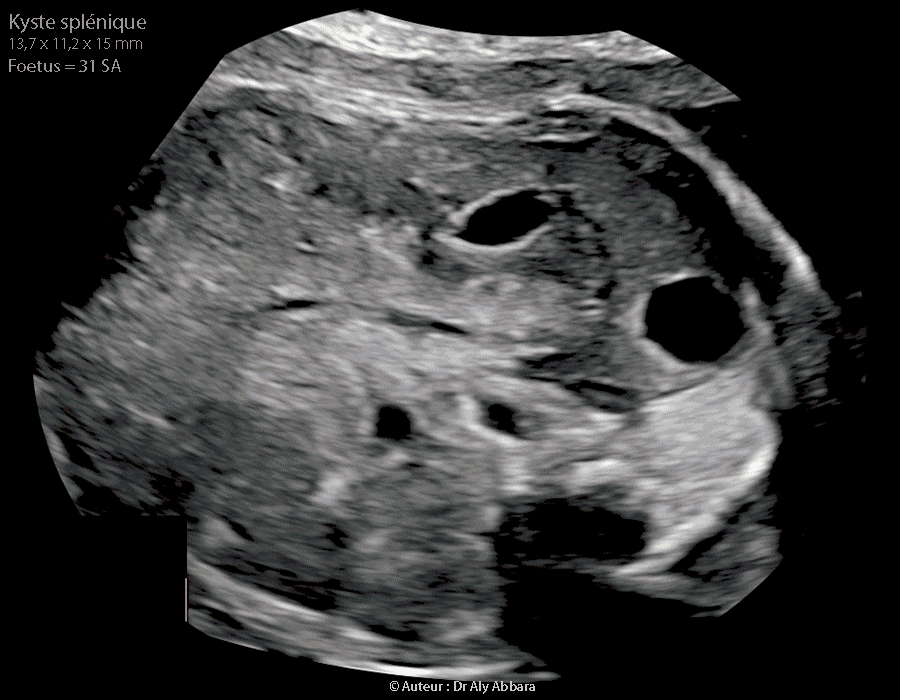

Rate Kyste Splenique Chez Un Foetus De 31 Sa Echographie